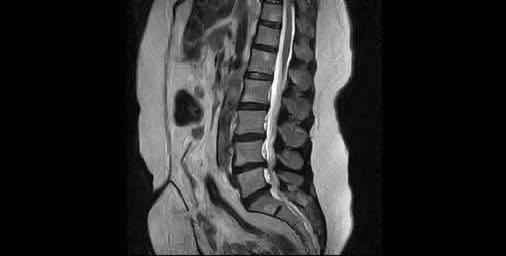

السلام عليكم لعد اخد رنين مفتوح ظهر لدي انزلاق كما موضوع بالصورة سؤالي هل يستوجب جراحة هل الانزلاق خطر ؟ و هل يسبب شلل او تلف ببعض أجزاء الجسم ؟

لا يتم تحديد الحاجة الى الجراحة ع ضوء الرنين فقط بل يحتاج الى اجراء الفحص السريري وتحديد اذا كان هنالك علامات طارئة تستدعي الحاجة الى الجراحة او عند عدم الاستجابة الى العلاجات التحفظية 0 2022-04-27T07:57:37+00:00